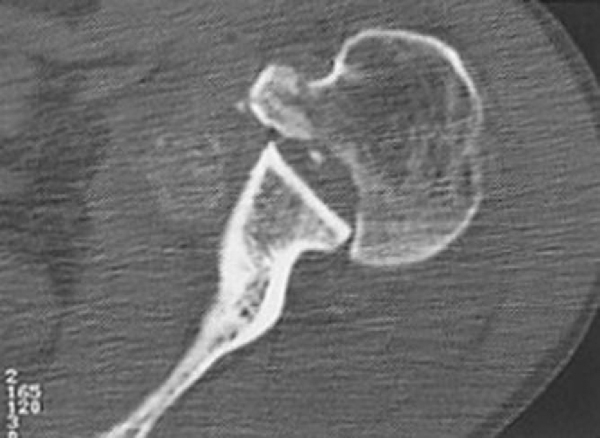

| • | Evaluate for glenoid version, locked dislocation ( Fig. 8-6 ) |

Figure 8-6 |